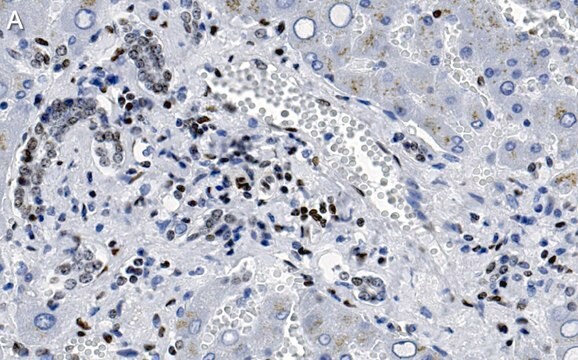

Immunohistochemistry (Paraffin) Analysis: A 1:100 dilution from a representative lot detected MeCP2 in human liver tissue sections.